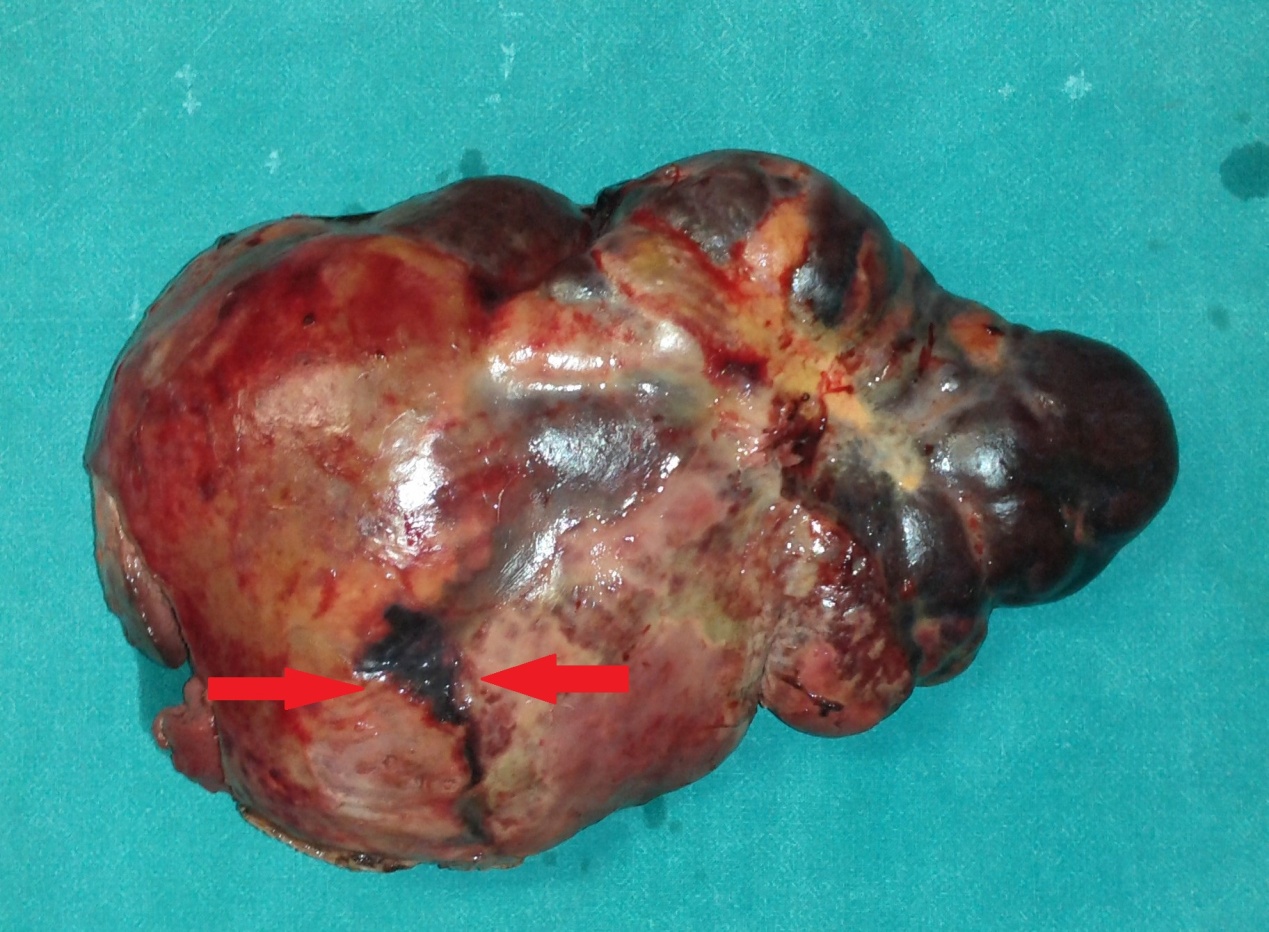

Undifferentiated sarcoma as the cause of the intussusception of the left hemicolon (Courtesy Dr. V. Penopoulos)